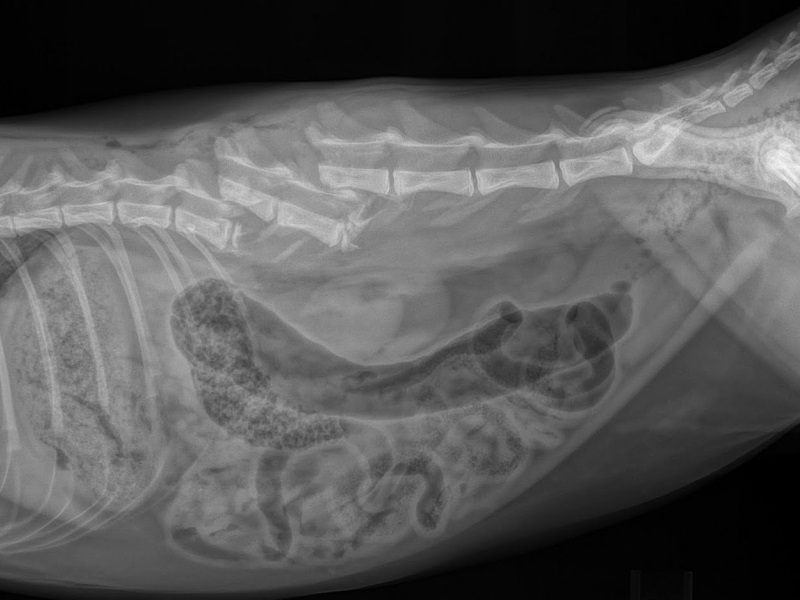

Диагноз ставится на основании рентгенографии и ультразвукового исследования, возможна серологическая диагностика (по типу антител, вырабатываемых к определенным разновидностям рака). Единственный шанс спасти животное – хирургическая операция. К сожалению, возможно ее осуществление далеко не в каждом случае.

В более тяжелых случаях отмечается ослабление или утрата безусловных рефлексов. Диагноз невозможно поставить без магнитно-резонансной томографии (MRI) или компьютерной томографии (CT), а также рентгена пораженных участков. При появлении неврологических признаков единственным способом лечения является оперативное вмешательство.